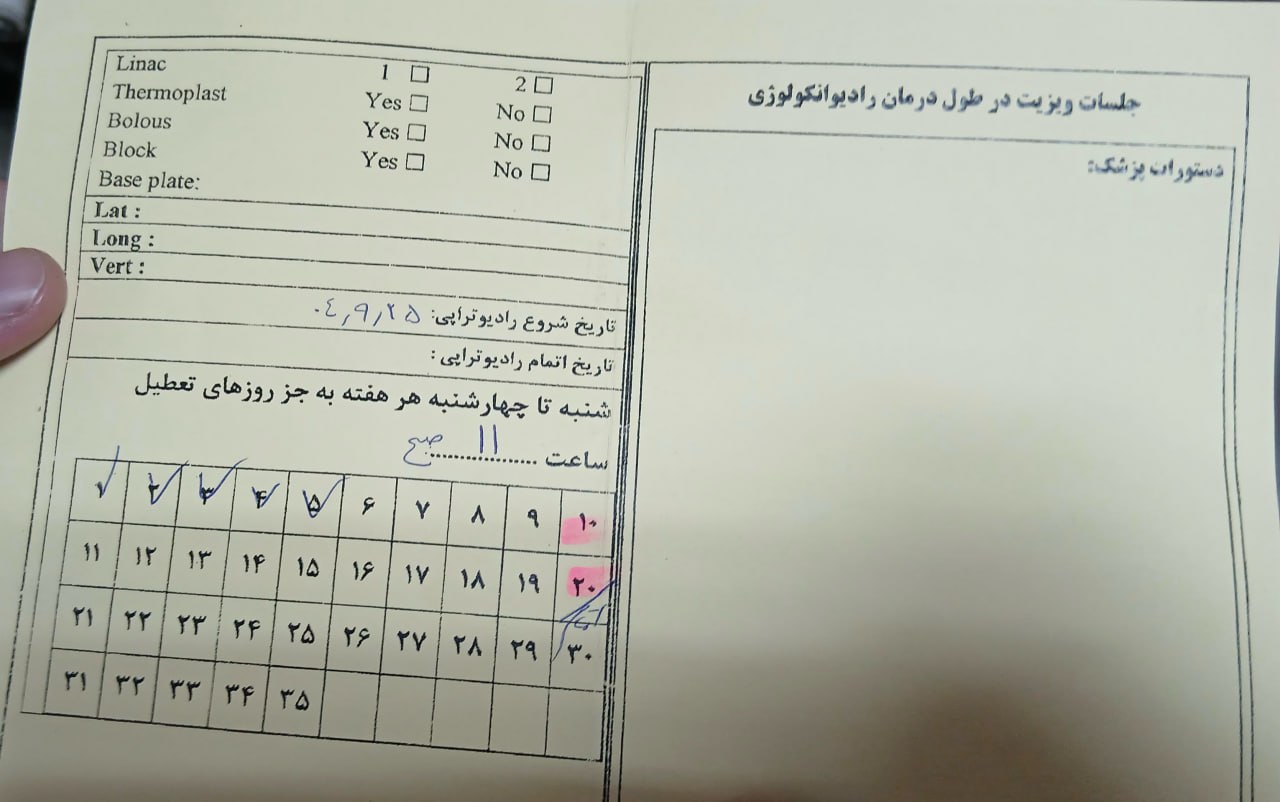

بیمار از حدود ۲۰ روز قبل برای پرتودرمانی به بیمارستان امام علی بجنورد مراجعه کرده و تاکنون ۱۲ جلسه پرتودرمانی دریافت کرده است.

(تصویر مربوط به این مراجعه نیست) Other:

(تصویر مربوط به این مراجعه نیست) Other:

(تصویر مربوط به این مراجعه نیست) Other:

(تصویر مربوط به این مراجعه نیست) Other:

به ترتیب؛ روز ها: ۱۹ آبان, ۲۸ آذر, ۲۹ آذر, ۳۰ آذر

به ترتیب؛ روز ها: ۱۹ آبان, ۲۸ آذر, ۲۹ آذر, ۳۰ آذر

۱۹ آذر

۱۹ آذر

به ترتیب؛ روز ها: ۲۸ آذر, ۲۹ آذر, ۳۰ آذر, ۱ دی

۱ دی